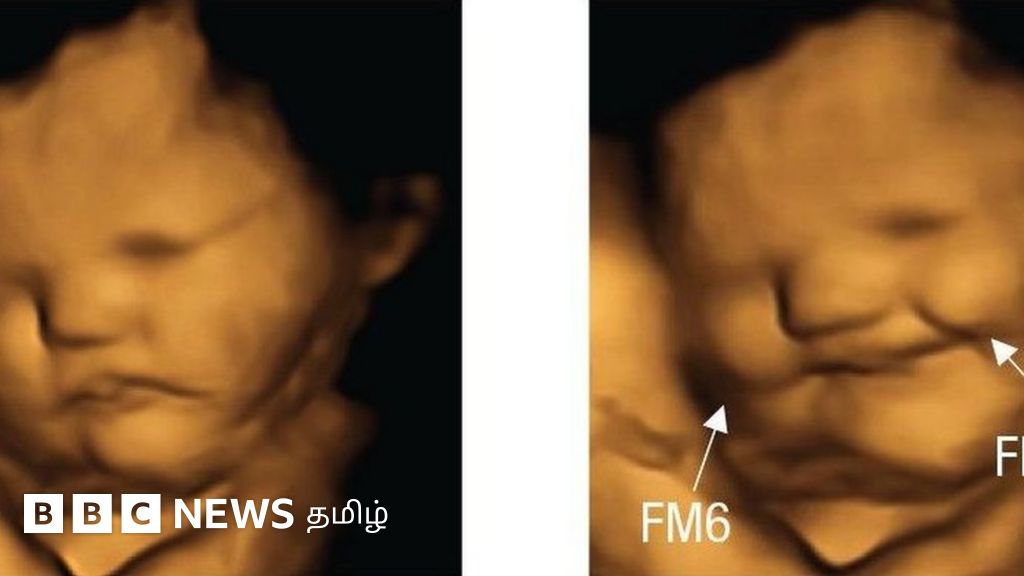

தாயின் கருப்பையில் இருக்கும் சிசு எந்த உணவுக்கு எப்படி எதிர்வினையாற்றும்?

தாய்மார்கள் கேரட்டைச் சாப்பிட்ட பிறகு, கருப்பையில் இருக்கும் சிசு புன்னகைப்பது போலவும், அதுவே கீரை சாப்பிட்ட பிறகு, முகசுளிப்பதைப் போலவும்